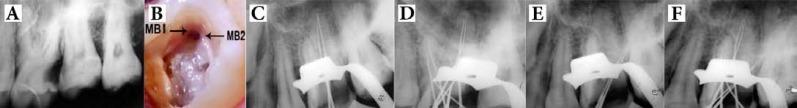

This case report presents a successful nonsurgical endodontic therapy of left maxillary first molar with three roots and seven root canals. This unusual morphology was diagnosed using a dental operating microscope (DOM) and confirmed with the help of cone-beam computed tomography (CBCT) images.

CBCT axial images showed that both of the palatal and distobuccal roots had Vertucci type II canal pattern, whereas the mesiobuccal root canal showed a Sert and Bayirli's type XV configuration.

The use of a DOM and CBCT imaging in endodontically challenging cases can facilitate a better understanding of the complex root canal anatomy, which ultimately enables the clinician to explore the root canal system, and therefore treat it far more efficiently.